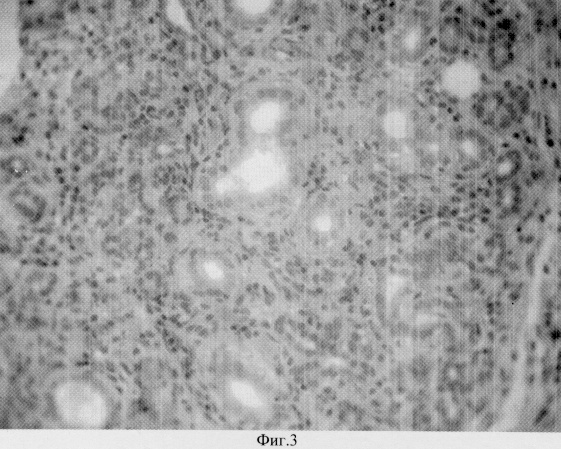

на фиг.3 – то же со стимуляцией комплексным аллогенным биоматериалом;

Предложенный способ был апробирован в серии экспериментов на белых крысах. Были проведены гистологические исследования щитовидных желез, на 30 сутки после резекции в группе без стимуляции (фиг.2 ) и со стимуляцией (фиг.3). В первом случае наблюдается выраженная лимфо-плазмоцитарная инфильтрация, разрушающая ткань щитовидной железы. Во втором случае (фиг.3) наблюдается снижение лимфо-плазмоцитарной инфильтрации в результате подавления аутоиммунной агрессии, видны типичные фолликулы щитовидной железы, новообразованные сосуды.